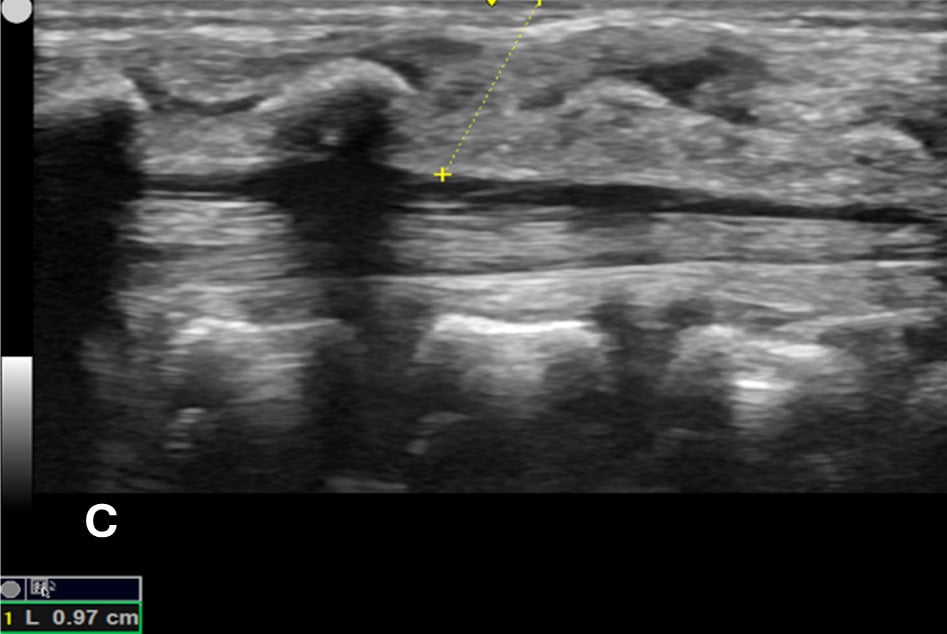

US-assisted LP is performed using the high-frequency linear transducer at the infant’s lower lumbar spine, with the patient either in a lateral recumbent position or an upright sitting position. The standard LP position, in which the neck and hips are flexed, should be used to locate the optimal site for needle insertion. Warm gel should be used during US to provide comfort and reduce the risk of hypothermia in infants. Align the transducer along the spinous process of the lumbar spine above the level of intercristal line to obtain a sagittal view of the spinal canal. The tapered CM is identified, below which any space is safe for needle insertion. The amount of anechoic cerebrospinal fluid (CSF) can be grossly compared in each space to locate the ideal LP site to obtain maximal CSF volume. (Figure 1A-B) The next step is to mark the skin at this optimal intervertebral level using a marking pen. Additionally, we recommend measuring the depth from the skin to the posterior border of the subarachnoid space using calipers, ensuring an angle of entry of 30–45 degrees. (Figure 1C) This allows the proceduralist to more precisely estimate the minimum needle depth needed to reach the subarachnoid space.

Figure 1C - The minimum depth from the skin to the posterior border of subarachnoid space for needle entry using calipers, which is measured at 0.97 cm (yellow dotted line).